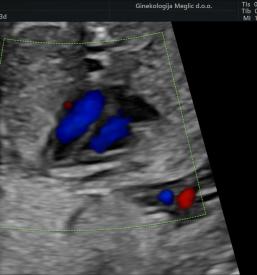

Če želite popoln nabor ginekoloških storitev, na katere ne boste čakali, vas bodo toplo sprejeli v Ginekologiji Meglič. V samoplačniški ginekološki ambulanti v Ljubljani oz. Bežigradu je skrb za paciente na prvem mestu.

V samoplačniški ginekološki ambulanti v Ljubljani oz. za Bežigradom so na najvišjem strokovnem nivoju zagotovljene vse storitve diagnostike in terapije na vseh področjih ginekologije in porodništva. Izpostavimo lahko zadovoljstvo strank, ko potrebujejo: